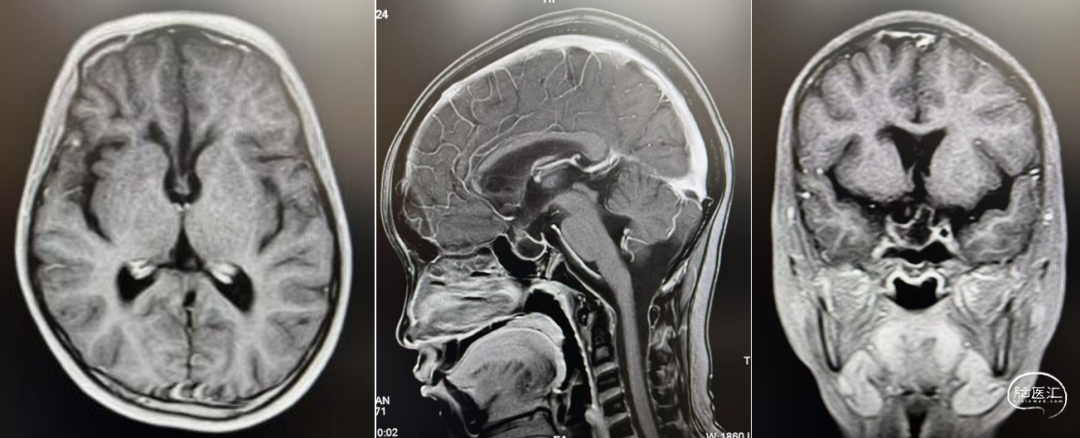

头部CT显示:左侧基底节区囊实性占位性病变,大小约40*36mm,内有多发钙化,低密度区CT值约12HU,临近脑实质密度减低,左侧脑室,邻近中线结构右移。

头部MRI显示:左侧基底节区囊实性肿块,内见实性成分及分隔,呈稍长T1稍长T2信号灶,FLARE呈高信号,大小约47*39*40mm,增强后实性成分及分隔明显强化。右侧侧脑室受压,周围脑实质可见条片状稍长T2水肿带,中线右移。

经纵裂胼胝体入路全切除病变。右侧肢体肌力4级。

病理检查:(左侧基底节)混合性生殖细胞肿瘤(50%生殖细胞瘤+50%胚胎性肿瘤)。免疫组化:CK-Pan(+),CD117(+),D2-40(+),Oct(+),AFP(部分+),PLAP(部分+),CD30(+),HCG(-),EMA(+),SALL4(+),Ki(约70%)。

术后建议辅助治疗。结疗后未见肿瘤复发,肌力已恢复至5-级。此后2年予以定期复查未见复发。

术后2年(已完成放疗化疗)